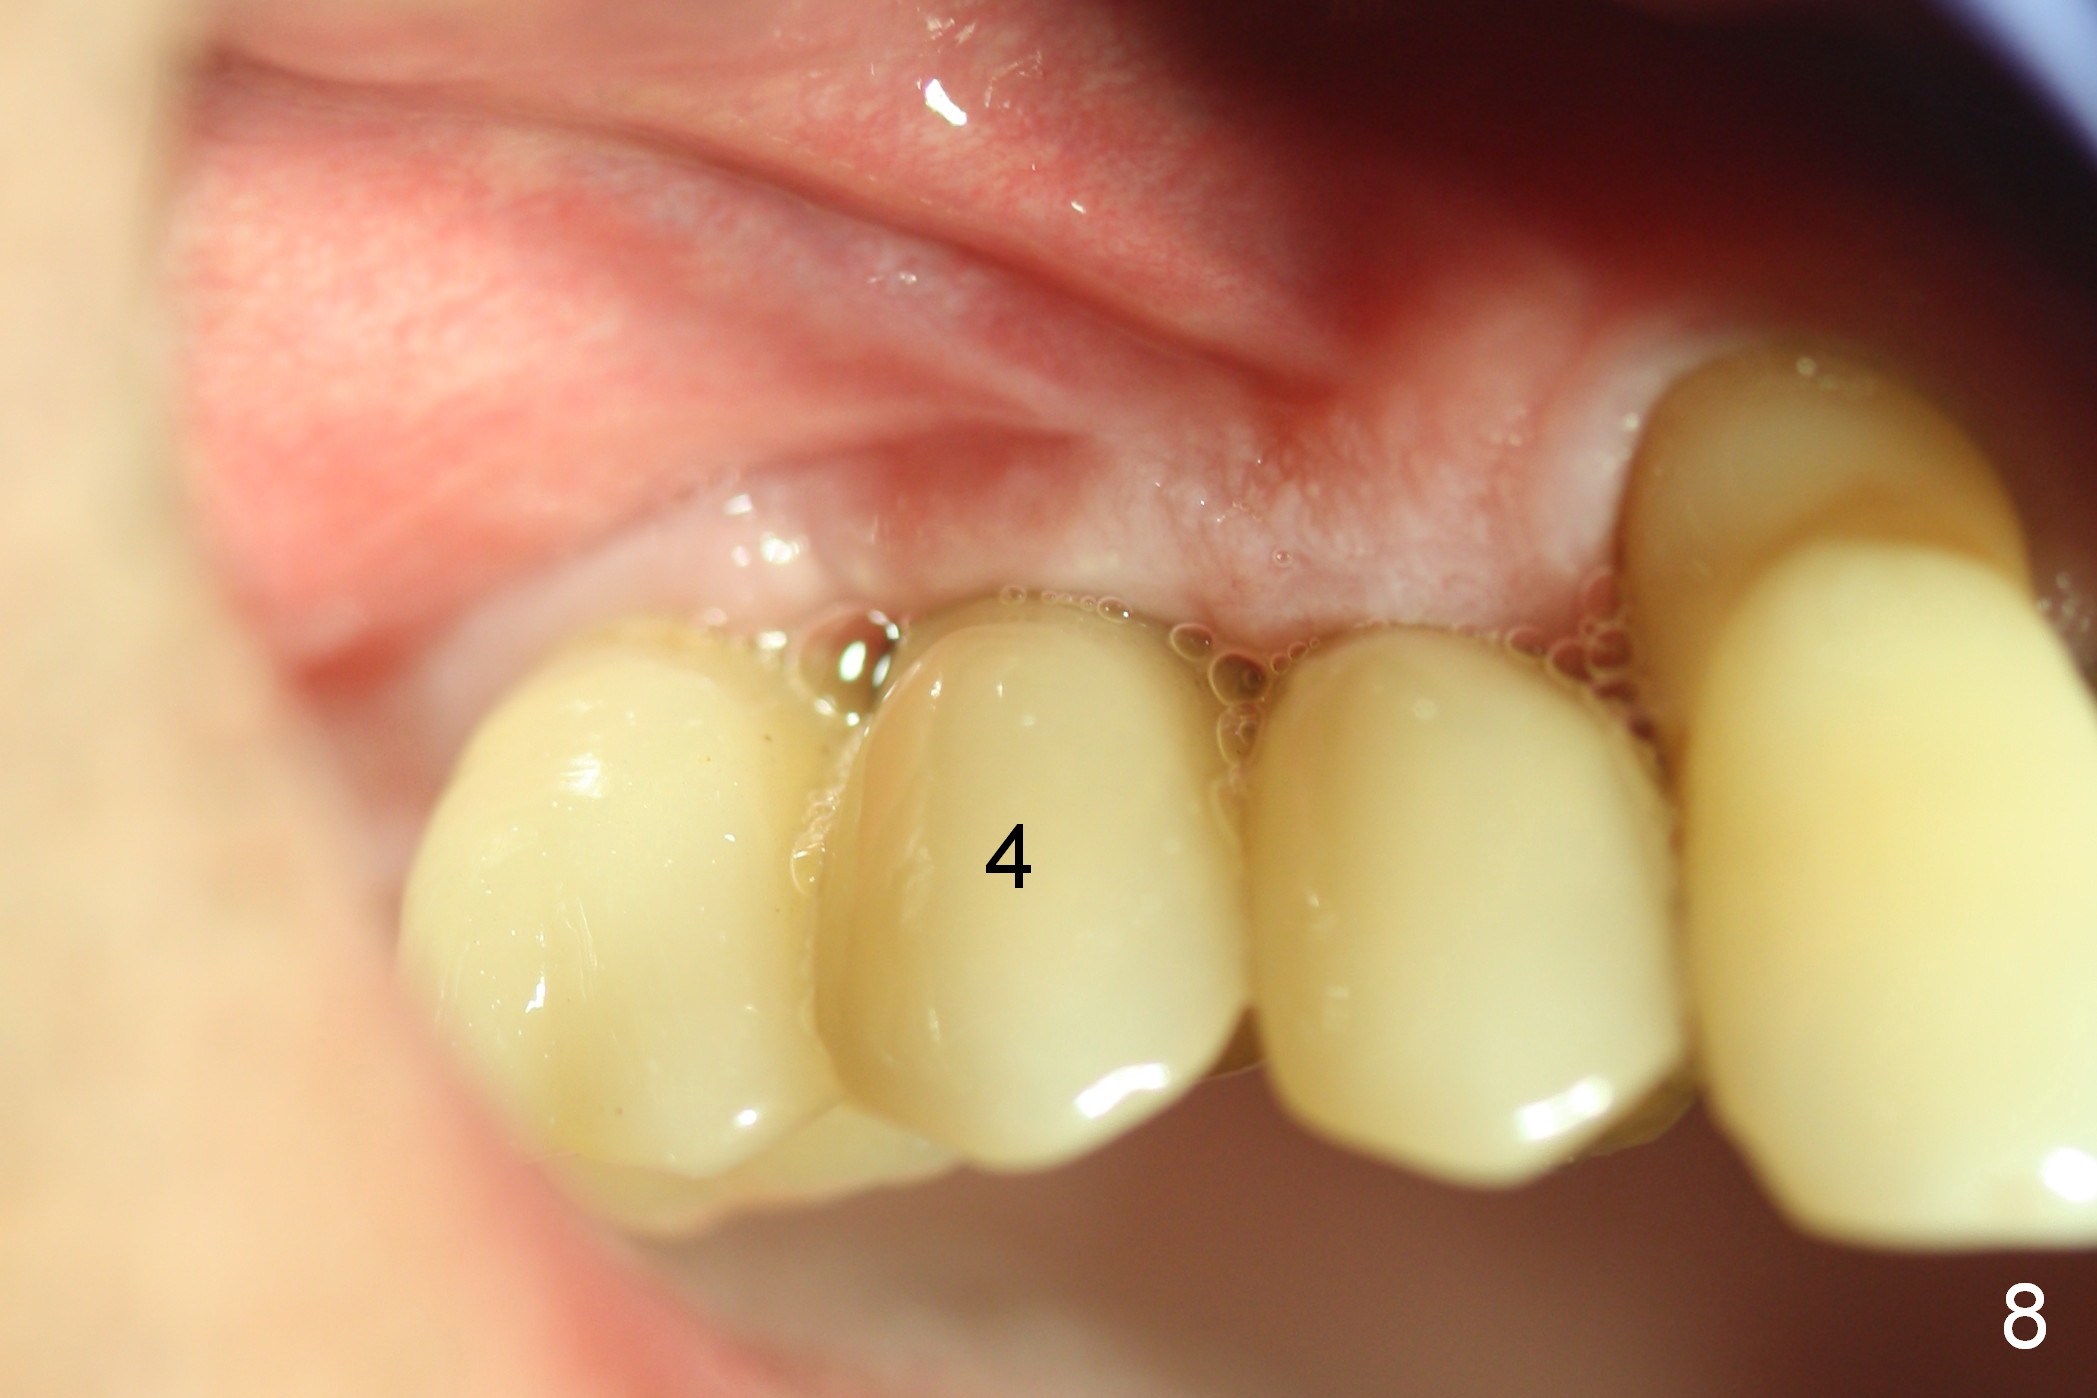

The patient returns for follow up 3 months postop. There is no gingival bleeding around the site of #4 palatally (Fig.7) or buccally (Fig.8). There is no further bone resorption (Fig.9).